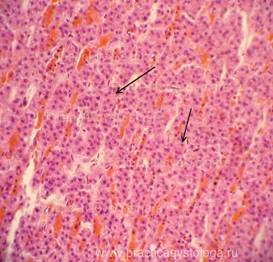

НАДПОЧЕЧНИК (1объект) -в срезах правого и левого надпочечников картина синдрома Уотерхауса-Фридериксена: чередующиеся выраженные очагово-диффузные деструктивные кровоизлияния насыщенно-красного и тёмно-красного цвета, с частичным гемолизом эритроцитов, умеренным и выраженным лейкоцитозом, очаги некроза коркового слоя надпочечников с умеренной и выраженной перифокальной лейкоцитарной инфильтрацией.Неравномерное кровенаполнение ткани надпочечников: чередование участков слабого его кровенаполнения и очагов капиллярно-венозного полнокровия. Неравномерно выраженная делипидизация (делипоидизация) цитоплазмы адренокортикоцитов пучковой зоны коры.

Рис. 1, 2. Надпочечник, корковый слой. Синдром Уотерхауса-Фридериксена. Окраска: гематоксилин и эозин. Увеличение х100 и х250.